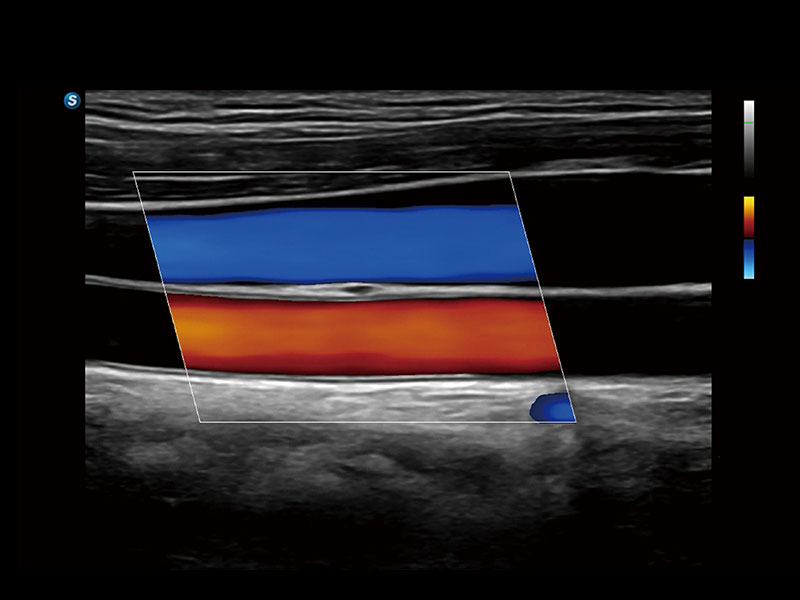

作为开立医疗全新打造的高端床旁笔记本超声,E11不仅具备卓越的图像质量,同时搭载全面高效的自动测量工具,助力医生实现更快速、更精准的床旁诊断。

E11搭载了丰富的自动化测量工具,以及专为POC科室定制的高级功能;同时配备了为急诊医师量身打造的 SonoFast急重症超声流程,以帮助临床医生最大限度的提升工作效率